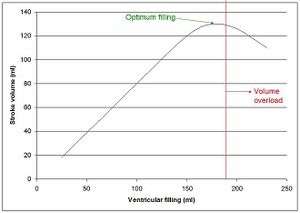

Goal in HF mgmt is to reduce preload (EDV) to reach higher SV on Frank Starling curve.